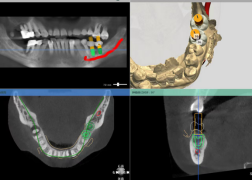

(锥形束CBCT为重建三围模型提供精准数据、计算机辅助设计软件辅助医生定制精准方案)

数字化种植牙就是指利用数字化技术辅助医生进行种植修复。在种植牙诊断和设计阶段,通过CBCT和口内扫描获取患者的口腔软硬组织信息,利用计算机辅助设计技术进行颌骨模型的三维重建,并在重建的模型上进行种植手术方案的设计,确定最适合患者的种植手术方案。在种植体植入阶段,利用计算机辅助制造技术,设计制作出种植导板,精确控制种植体植入位置、角度及深度,使种植体的植入更加精确、微创、高效。在种植牙修复阶段,可以采用口腔扫描的方式进行印模制取,取代传统的咬牙印的方式,避免患者恶心,提高患者的舒适度。

数字化种植牙采用3D数字打印技术制作导板,为种植体的植入进行精确的定点,三维虚拟模型设计植入种植体,避开重要结构位置,最大程度的利用患者现存骨量,优化种植体的位置。

数字化种植技术是在电脑上建模,模拟种植体的最佳植入方式,导板铺助定位置、定深度、定方向,避开重要的结构位置,避免了一些植入方式不当造成的神经创伤或穿透至鼻窦腔的问题。